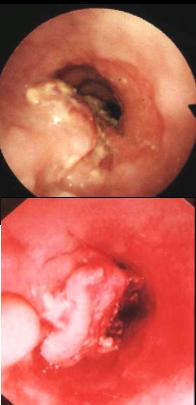

Image fibroscopie de oesophage :

Lesion en bourgeon de carcinome epidermoide .

Diagnostic ( + ) envue sur anapath |